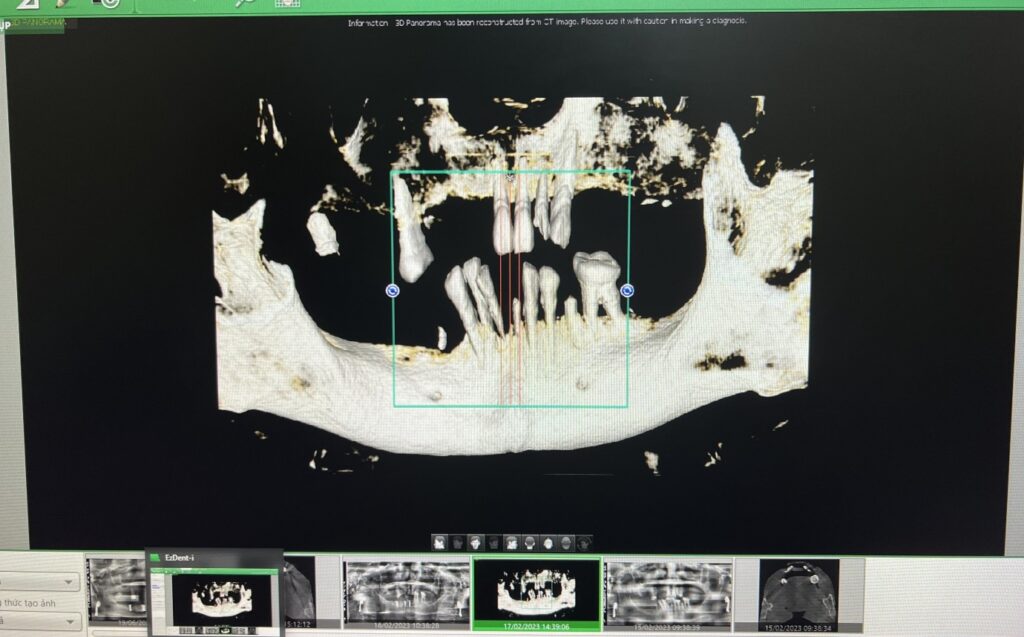

Máy chụp CT Cone Beam 3D là hệ thống chụp X-quang 3D giúp bác sĩ biết chính xác độ rộng, sâu của xương. Ngoài ra, phim chụp X-quang bằng hệ thống Cone Beam CT còn cho thấy rõ mối liên quan giữa răng hàm dưới và dây thần kinh, mối liên quan giữa răng hàm trên và xoang hàm, có thể tầm soát các tổn thương sâu và chi tiết.

Phim 3D CT Cone Beam hỗ trợ đặt implant. Bác sĩ có thể xem mật độ xương để tiên lượng có cần ghép xương hay không và lựa chọn trụ implant có đường kính phù hợp nhất với ổ xương. Thông thường, nếu không có phim 3D Cone Beam CT, bác sĩ sẽ dự đoán đường kính implant bằng cách đo chiều rộng xương theo phương pháp thăm khám lâm sàng hoặc chọn implant có đường kính nhỏ nhất để cấy ghép an toàn. Tuy nhiên, implant sẽ không có tuổi thọ cao. Vì những lý do trên, cấy ghép implant với sự hỗ trợ của máy phim CT Cone Beam 3D sẽ mang lại hiệu quả tốt hơn rất nhiều.

Phim 3D CT Cone beam để đánh giá tương quan giữa răng hàm trên và xoang hàm tránh trường hợp implant bị rơi vào xoang hàm. Mối tương quan giữa răng hàm dưới và dây thần kinh hàm dưới để implant không đè lên dây thần kinh. Đây là thông tin lâm sàng quan trọng để sau khi đặt implant không gây tổn thương.

– Trong khi chụp X-quang toàn cảnh chỉ cho thấy 2 chiều không gian trên và dưới, biết được chiều cao của xương hàm thì 3D CT Cone Beam cho biết được chiều rộng và chiều sâu của xương.

– Phim toàn cảnh chỉ cho thấy hình ảnh của tổn thương, nhưng CT Cone Beam 3D sẽ cho thấy mức độ xâm lấn của tổn thương.